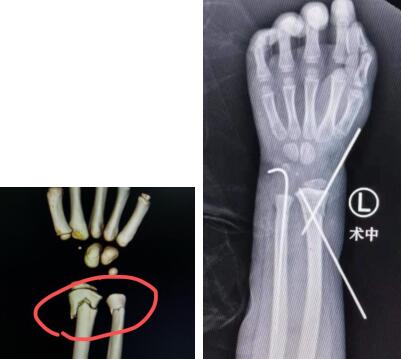

考虑到小昊明年龄小,去专科大医院才能放心,于是爸爸妈妈带着小昊明来到betway在线登陆。手外三李刚医生正在手外科急诊值夜班,接诊后,他耐心安抚了小朋友及父母,安排小昊明住院。7月26日,李医生主刀为小昊明做了左尺桡骨远端骨折复位内固定术。手术很成功,小昊明的爸爸妈妈非常满意。

术前(左图) 术中(右图)